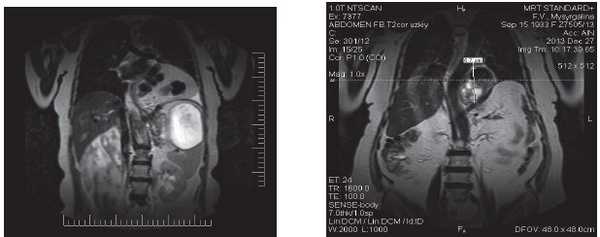

МРТ диафрагмы проводилась в случаях, когда постановка диагноза вызывала затруднение, а также с целью измерения грыжевого дефекта в диафрагме и выбора метода круропластики (рис. 3).

Рис. 3. МРТ диафрагмы, органов верхнего этажа брюшной полости: а - объемное образование в области левого реберно-диафрагмального угла размерами 11,0×11,5×10,9 см с наличием гипоинтенсивных округлых сливных включений - петля поперечной ободочной кишки вместе с большим сальником. На снимке (б) отчетливо визуализируется пролабирование дна желудка выше пищеводного отверстия диафрагмы на 6,7 см, диффузное накопление контраста измененной стенкой желудка размером 8,0×5,8×5,6 см, размеры пищеводного отверстия - 5,1×3,3 см